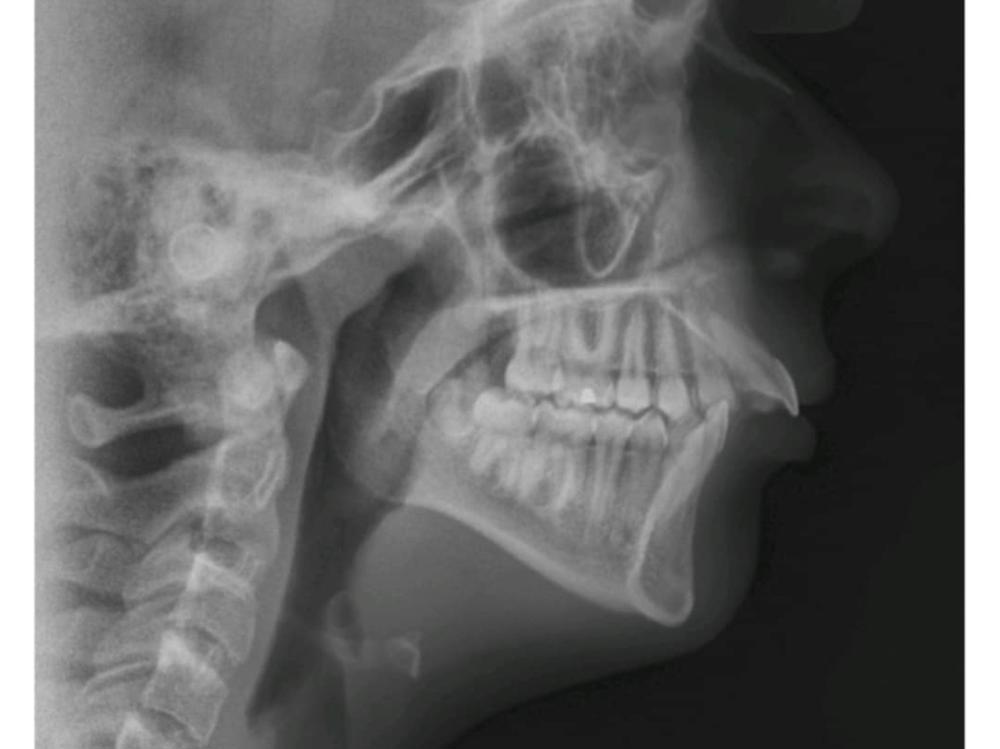

The reason for her attending is she has a very significant overjet - a dental condition where the top front teeth protrude horizontally past the bottom front teeth. This causes her great discomfort and among other things affects her eating, with a sensation of her teeth feeling loose, especially triggered by hard foods - a very uncomfortable feeling! The overjet can also lead to further dental issues such as tooth wear, gum damage, difficulty chewing or speaking, and heightened risk of injury should she fall or otherwise hurt herself.

In 10-12 months she will undergo what is called a bilateral sagittal split osteotomy (BSSO) for mandibular advancement, which involves the oral surgeon making cuts to Lily’s lower jawbone to reposition and stabilise it with plates and screws.

There is further likelihood she will need a genioplasty, a type of chin surgery to realign and reshape her chin after the BSSO procedure.